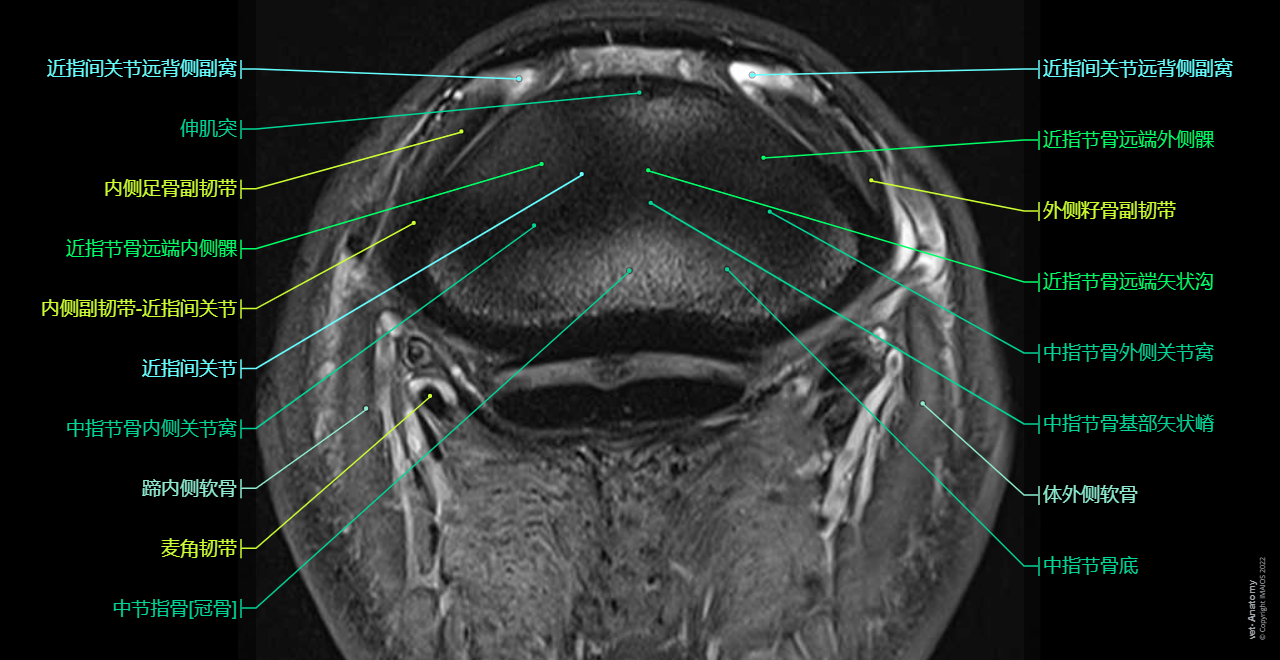

Digit - Horse: MRI - T2-STIR (Transversal)

Horse - Cross-sectional anatomy (MRI - CLL PD): Lateral collateral sesamoid ligament, Medial collateral sesamoid ligament, Lateral collateral ligament - Distal interphalangeal joint [Coffin joint; DIP joint], Distal digital annular ligament